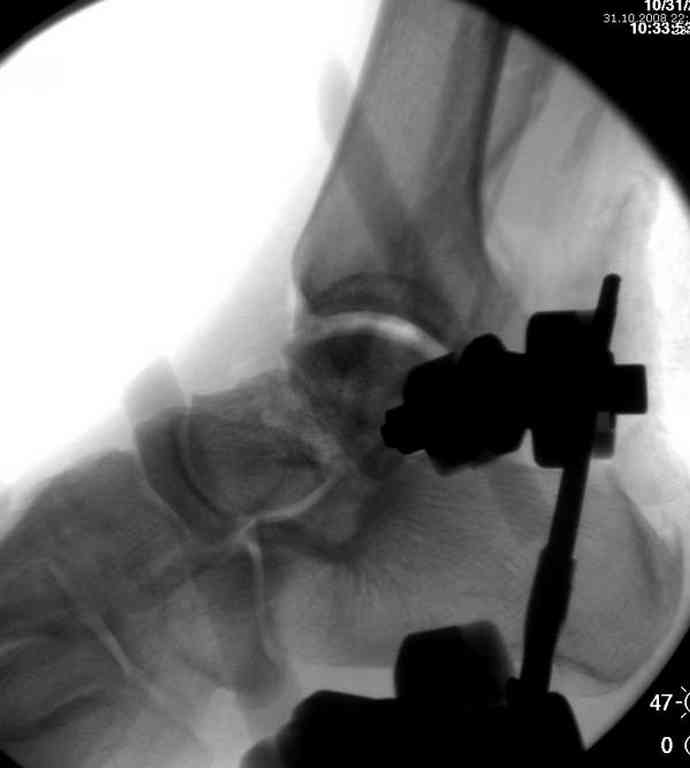

10 дней назад поступил с открытым повреждением медиальной лодыжки и переломо вывихом таранной кости. Ургентно сделана репозиция с наложением наружного фиксатора + Irrigation&Debridment.

Во время репозиции выявили повреждение заднего сухожилия м. тибиалис и задней большеберцовой артерии. Медиальную рану удалось закрыть частично и установлен вакуум.

Вчера провели фиксацию.

Из-за многооскольчатости дистальной части малоберцовой, где невозможно было провести фиксацию шурупами, перелом зафиксирован подпирающей пластиной, которая должна служить дополнением отсутствующей дистальной части малоберцовой (lateral cortex substitute).

Для стабильности два шурупа на синдесмоз.

Медиальную рану с приближенными краями продолжаем вакуумировать (KCI). Наружный фиксатор оставлен на пару недель, надеюсь, небольшая рана будет гранулировать и закроется без кожной пластики. Фиксация медиальной ложыжки не планируется.